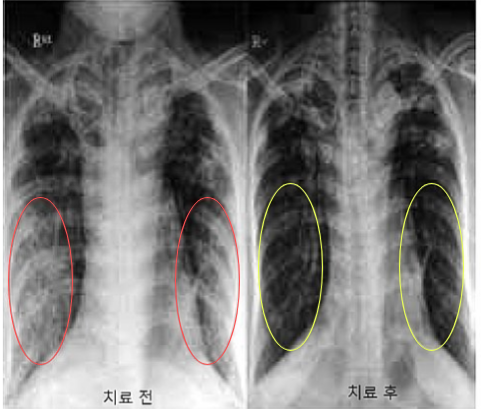

줄기세포 치료 가능성이 확인된 분야 중 하나가

만성폐쇄성폐질환(Chronic Obstructive

Pulmonary

Disease, COPD)

이다. 담배연기나 매연, 미세먼지, 세균과

바이러스 등의

위험인자에 오랫동안 노출돼 기도와 폐에

만성적인 염증이 생겨

기도가 좁아지는 병을

말한다.

전 세계적으로 COPD 치료법 개발을 위한 줄기세포 임상

연구들이 수천 명을 대상으로 진행됐거나 진행되고 있다.